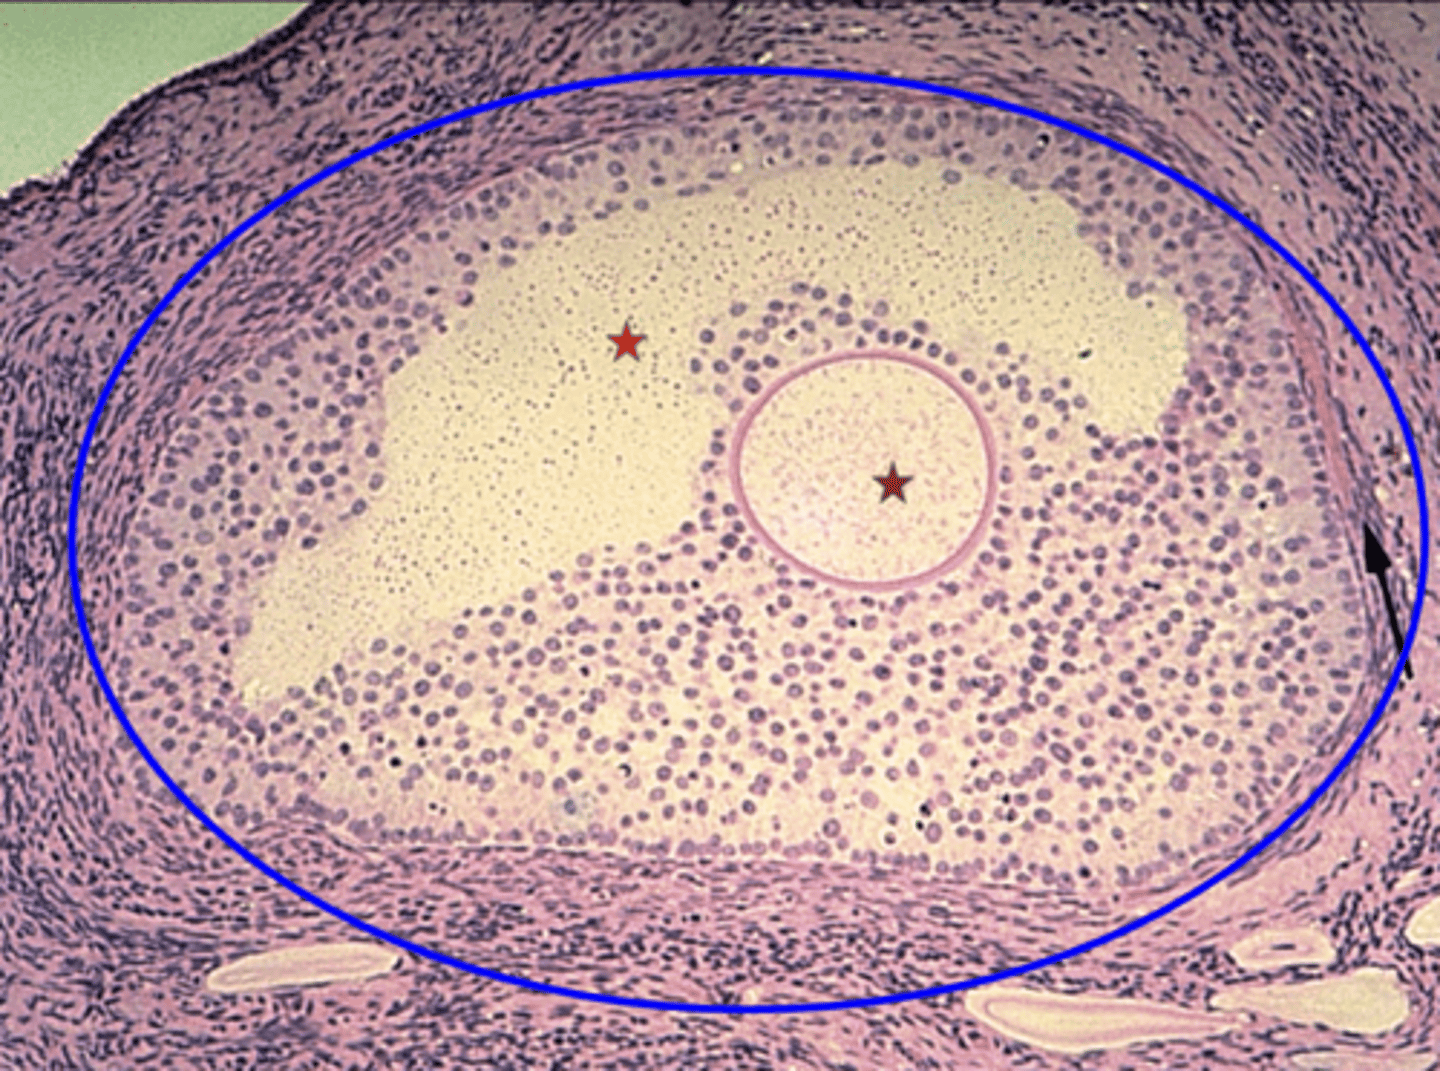

Germinal epithelium

What is the black arrow?

Tunica albuginea

What is the red arrow?

Primordial follicles

What is the green circle?

Multilaminar primary follicle

What is the blue outline?

Primary oocyte

What is the red star?

Secondary follicle

What is the blue circle?

What is the brown star?

Developing antrum